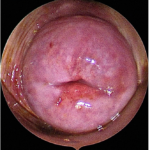

A hysteroscopy is a procedure that allows your doctor to look inside your uterus (womb) to diagnose and treat causes of abnormal bleeding or fertility issues. We use a hysteroscope-a thin, lighted telescope-like instrument. It is inserted through the vagina and cervix into the uterus. Because it enters through natural pathways, there are no cuts or incisions on your skin.

1. Diagnostic Hysteroscopy: Used to simply “look” and diagnose problems like polyps, fibroids, or structural issues.

2. Operative Hysteroscopy: If a problem is found during the diagnosis, we can often use specialized, slender instruments to correct the issue mmediately (e.g., removing a polyp).